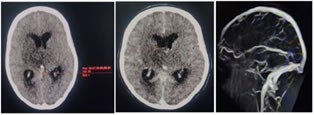

CASE 2-

Figure 2: 26years old female patient presented with altered sensorium and 1 episode of seizure

A: Axial plain CT shows bilateral thalami infarct with hyperdense straight sinus; B:Axial contrast CT image shows non opacification of straight sinus confirming thrombosis, C:MR Venography shows occlusion of straight sinus

Hounsfield unit (HU)-63 ; Haematocrit (HCT)-42% ; HU: HCT=1.5 HU: HCT=1.61